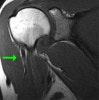

MRI : 상완 이두근 근위부 파열(Proximal biceps tendon rupture)